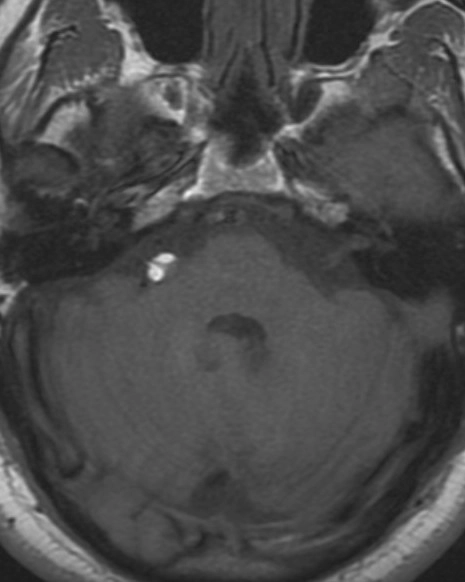

Nang màng nhện góc cầu tiểu não (CPA-IAC Arachnoid Cyst)